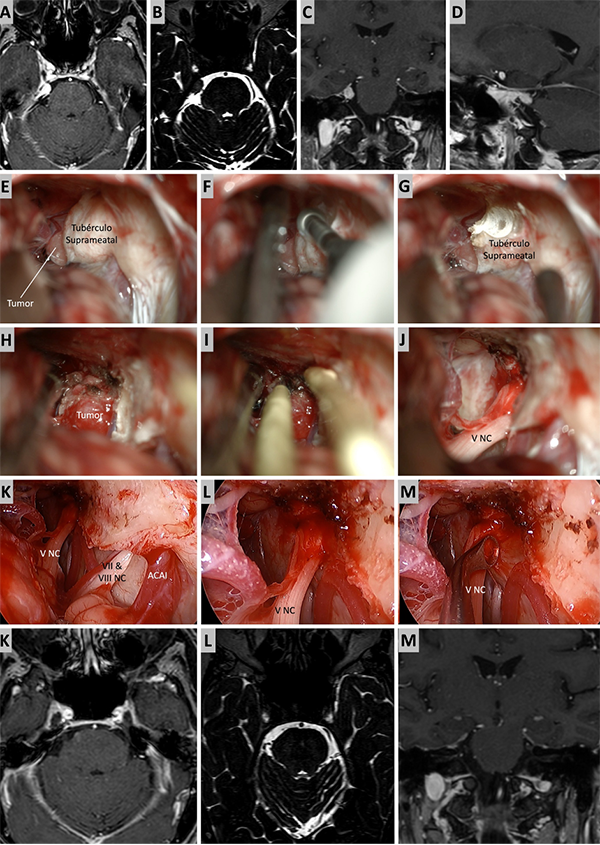

Figura 5. Caso ilustrativo #3. A-D. Resonancia que muestra MRPC con implantación clival. E-J. Se realiza un abordaje retrosigmoideo, consiguiendo la liberación del complejo VII-VIII del tumor y su resección completa. K-M. Resultado imagenológico postquirúrgico.

Figura 6. Caso ilustrativo #4. Meningioma de la MRPC con implantación petrosa anterior. El paciente presentaba neuralgia del trigémino atípica derecha. A-D. Imágenes por RMN pre operatorias. E-J. Se realiza un abordaje retrosigmoideo consiguiendo la resección total del tumor. K-M. Con ayuda de endoscopio y lente con angulación de 30º se inspecciona el área sin encontrar remanente tumoral. Se observa liberación del nervio trigémino. K-M. RMN postoperatoria que muestra resección total.